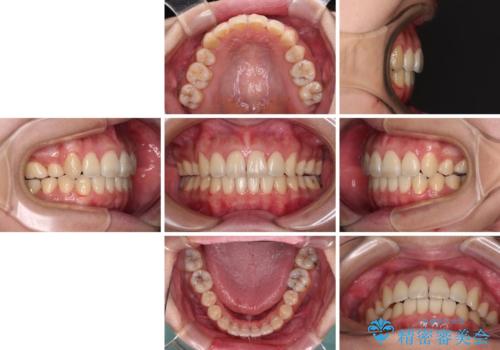

- 八重歯と叢生を気にして来院された患者様です。

上下の前歯が非接触であり、叢生や八重歯が顕著であったため、上顎左右第一小臼歯2本を抜歯して排列することとしました。

抜歯により移動量が多くなるため、ワイヤーや補助装置を活用し、その後インビザラインによる矯正治療を行うこととしました。

元々奥歯に負担のかかる咬み合わせですり減っていたため、仕上がった歯並びでも奥歯が咬んでいないように見えましたが、実際にはしっかりと咬合しており、患者様本人も咬んだ感触に違和感はないとのことでした。